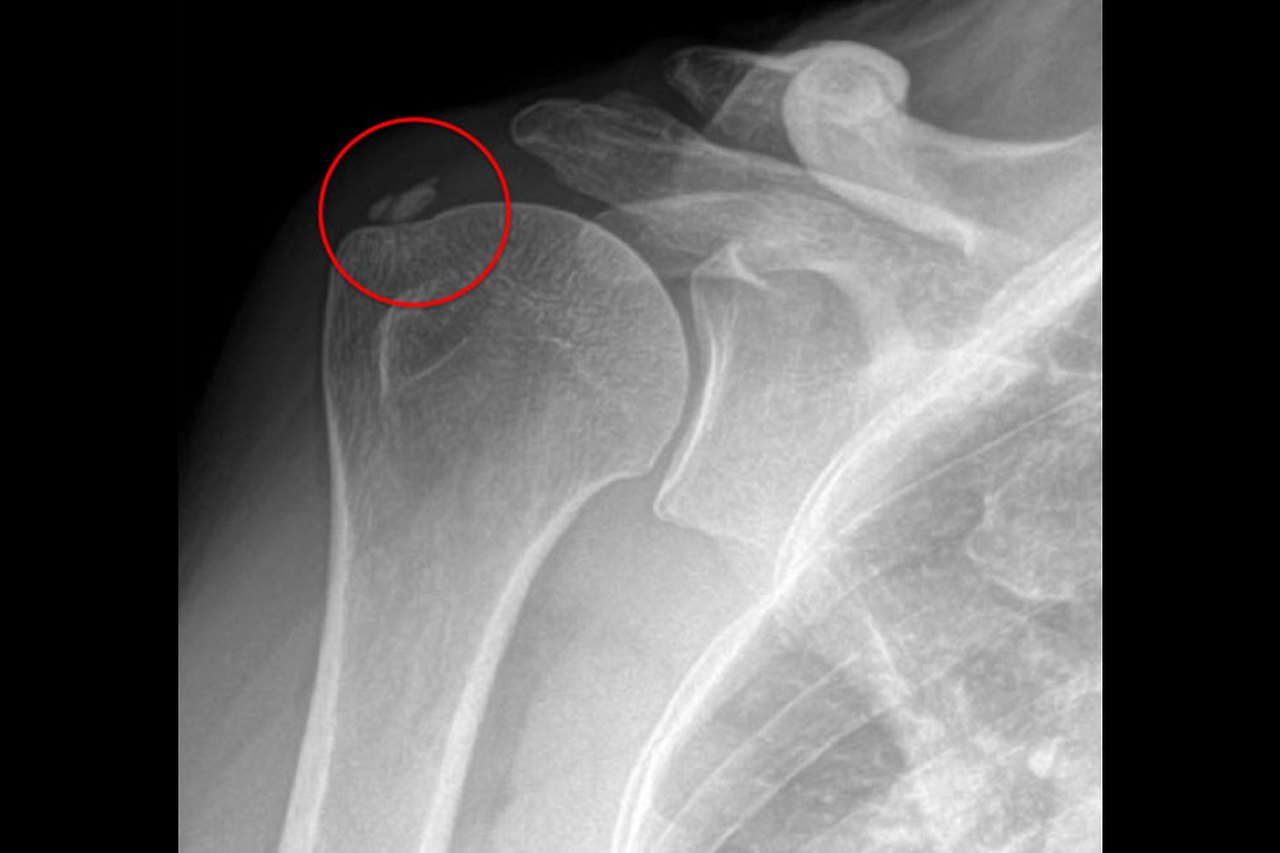

210617_석회성건염_01.jpg

석회성건염은 어깨힘줄에 석회(칼슘)가 침착하여 통증 및 운동장애를 일으키는 병을 석회성건염이라고 합니다. 간혹, 증상이 없이 석회가 침착하였다가 사라지기도 하지만, 경우에 따라서는 매우 극심한 통증을 초래하는 경우들도 있으며, 통증이 심한 경우에는 마치 종기가 곪은 것 같다고 해서 ‘화학적 종기’라는 별명을 갖고 있습니다.

통증이 너무 심해 환자가 응급실을 찾게 되는 경우도 종종 있으며, 외래 진료실에서도 통증 때문에 팔을 건들지도 못하게 할 정도로 진찰이 어려울 때도 있습니다.

석회성건염은 어깨 회전근개 힘줄에서 가장 많이 발생하게 되며, 그로 인해 어깨의 움직임에 제한이 생기기도 합니다. 가장 흔하게 석회가 침착하는 힘줄은 극상건이며, 그 외 견갑하근, 극하근 등 다른 회전근개에도 침착될 수 있습니다.

석회성건염 환자들에게는 석회가 힘줄에 단단하게 박혀있는 상태를 휴지기(분필모양)라고 하며, 이때는 극심한 어깨통증보다는 어깨를 움직이다보면 특정각도에서 통증이 발생하는 경우가 많습니다. 이시기에 충격파치료를 가장 많이 받게되나, 수차례 포커스타입의 충격파로 치료를 받더라도 석회가 잘 안깨지는 경우가 많은데, 이는 충격파치료 특성상 석회위치를 정확히 찾아서 보면서 시행하지 못하고 석회가 박힌 힘줄부위에 넓게 위치를 옮겨가며 치료하기 때문에 충격파 에너지가 석회에 정확하고 충분히 전달되지 못하기 때문이며, 그결과 수차례 충격파 치료를 받았음에도 석회는 깨지지 않고, 남아있으며 오히려 통증만 심해지는 경우들이 발생하게 됩니다. 이때에는 석회의 위치를 초음파로 정확히 확하고 보면서 굵은 바늘을 이용하여 석회를 부수어 내고, 흡인하여 제거하는 "석회분쇄흡인술(Barbotage)"을 핌스(PIMS)치료에 더해서 시행한다.